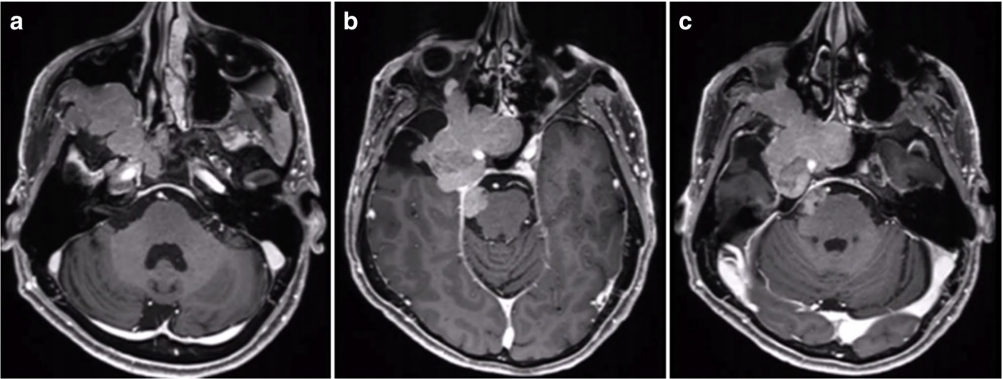

53岁男性患者,7年前在外院手术切除2级脑膜瘤。因出现三叉神经V1、V2区麻木,V3感觉迟钝入院。MRI见较大脑膜瘤复发侵犯右侧海绵窦、眶顶、SphS、PPF和ITF并通过Meckel’s腔(MC)延伸至小脑桥脑角(CPA)(图a-c)。

采用原额颞入路,打开SOF,切除眶外侧壁,打开FO和FR,磨除前部颞窝底、IOF外缘、ALT和PP。切断眶颞骨膜反折,从CS上将颞窝硬膜剥下。打开硬膜,切除硬膜下颞部肿瘤。从上方打开MC,继续切除突入CPA的肿瘤。磨除ALT和PP,切除ITF的肿瘤。打开AMT,切除OM。将进入PPF、突入CS前部的肿瘤切除。然后在内镜观察下切除伸入SphS的肿瘤。用骨膜严密修补缝合硬膜,去除蝶窦粘膜并填入脂肪。术后MRI显示肿瘤全切除。

(PPF,翼腭窝;ITF,颞后窝;SphS,蝶窦;MC,Meckel腔;CPA,小脑桥脑角;ALT,前外侧三角;AMT,前内侧三角;ZN,颧神经;V2,三叉神经上颌支。)